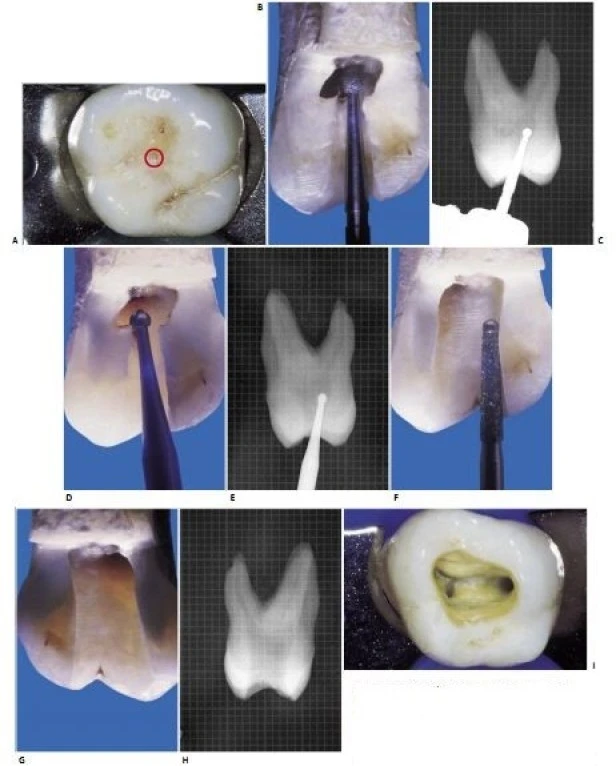

Hầu hết các tác giả mô tả xoang tủy của răng cối lớn hàm trên và dưới có dạng tam giác với điểm đi vào nằm về phía gần hơn (hình 11.71 A-D). Tuy nhiên, vì sàn tủy răng cối lớn có hình tứ giác nên rõ ràng rằng xoang tủy cũng nên có hình dạng tương tự.

Như đã phát biểu ở trên, xoang tủy có thể được xem là hình chiếu của sàn tủy lên mặt nhai. Vì vậy nó phải có hình tứ giác với các góc tròn (hình 11.71 E-G). Cạnh ngắn nhất của tứ giác thường là cạnh trong; cạnh tiếp theo dài hơn là cạnh ngoài, cạnh này hơi nghiêng vào trong vì ống xa hơi nằm về phía trong; tiếp nữa là cạnh xa và dài nhất là cạnh gần. Vì sàn tủy nằm giữa các thành bên, Acosta Vigouroux và Trugeda Bosaans nhận thấy trong 134 răng đã nhổ thì sàn tủy nằm chính xác giữa thân răng. Ta phải luôn lưu ý đến điều này để sửa soạn một xoang tủy đúng.

Hình 11.71. A. Mặt nhai răng cối lớn một trên. B. Tạo xoang tủy hình tam giác với vị trí mở vào nằm về phía gần. C. Xoang tủy dạng tam giác đã hoàn thành. D. Đưa dụng cụ vào ống trong, nó không đi thẳng được đến 1/3 chóp mà bị cản lại bởi gờ ngà. E. Hình dáng xoang tủy nên là hình chiếu của sàn tủy lên mặt nhai. F. Xoang tủy đúng khi hoàn thành có hình tứ giác với các góc tròn. G. Xoang tủy răng cối lớn thứ nhất có hình một tứ giác không cân xứng. Các ống tủy đã được làm sạch và tạo hình.

Bắt đầu tạo xoang tủy với các một mũi khoan kim cương tròn, tay khoan siêu tốc, đặt tại rãnh giữa. Nghiêng mũi khoan hướng về phía sừng tủy mà trên X-quang thấy là rộng nhất, thường là sừng tủy phía trong (hìnhs 11.72 A-C). Dùng mũi khoan tròn, dài, thuôn và tay khoan chậm lấy đi phần ngà còn dính lại, chạy mũi khoan trên đường đi ra của mũi khoan. (hìnhs 11.72 D-E). Cuối cùng, dùng mũi khoan tự hướng dẫn và tay khoan siêu tốc trong giai đoạn hoàn thành và làm loe (hìnhs 11.72 F-I).

Hình 11.72. A. Điểm vào của mũi khoan. B. Hoàn thành giai đoạn xuyên qua. C. Để tránh tối đa việc phạm vào sàn tủy, mũi khoan nên hướng về nơi buồng tủy cao nhất. D, E. Dùng mũi khoan loại bỏ phần còn lại của trần tủy. F. Dùng mũi khoan tự hướng dẫn trong giai đoạn hoàn thành và làm loe. G. Xoang tủy khi hoàn thành. H. Hình ảnh X-quang xoang tủy. I. Xoang tủy nhìn từ mặt nhai

Nếu gặp phải khó khăn khi tìm ống tủy thì nên bắt đầu sửa soạn ống trong trước (ống này rộng và thẳng nhất nên làm dễ nhất). Bơm rửa bằng NaOCl sẽ giúp định hướng và tìm miệng các ống tủy khác dễ dàng hơn.